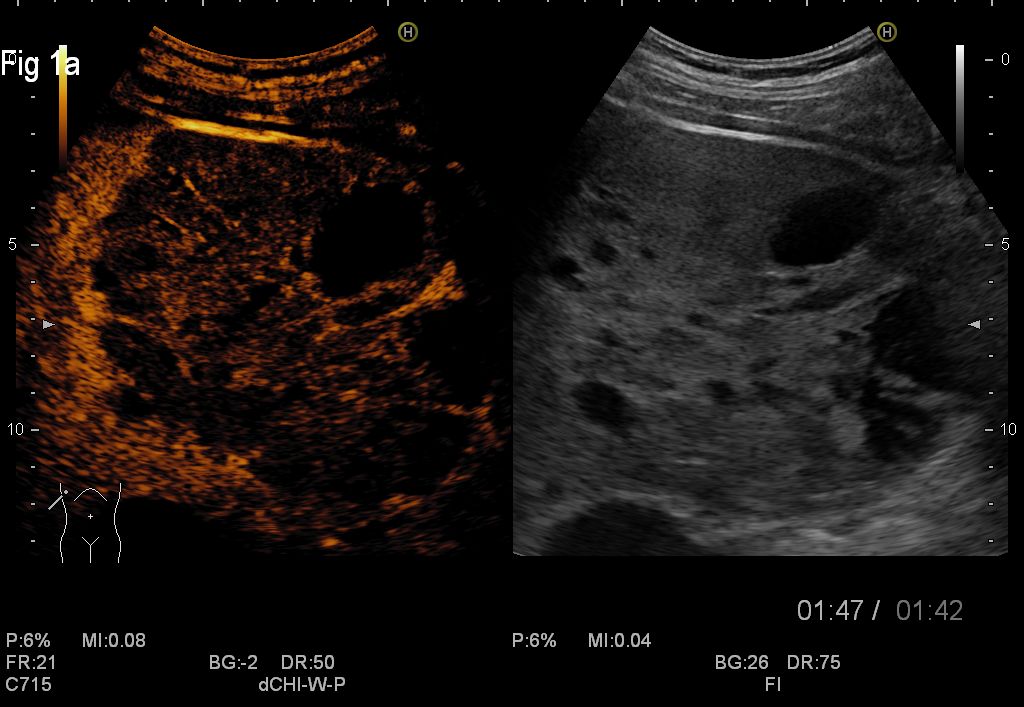

Conventional abdominal ultrasound revealed numerous well-demarcated masses in the right liver lobe, with internal septations and mixt content, transonic and hypoechogenic.

CEUS showed enhancement in the arterial phase and slow wash-out in the late venous phase at the periphery with central necrosis in some of the masses, which excluded the diagnosis of hydatid cyst and was suggestive for a malignant pattern.